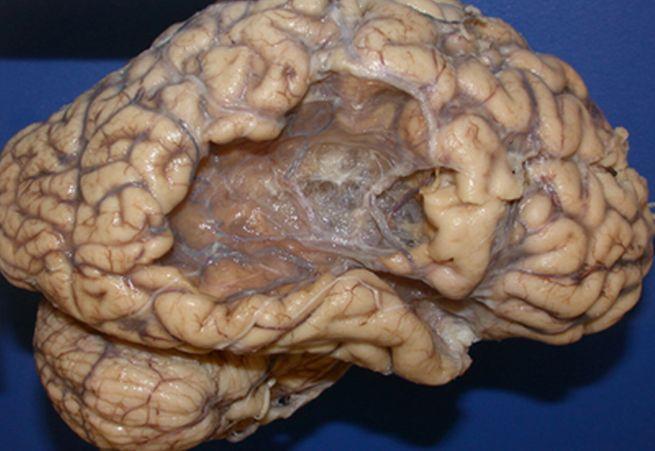

Cum arată CREIERUL UMAN după un ATAC CEREBRAL

Foto: neuropathology-web.org